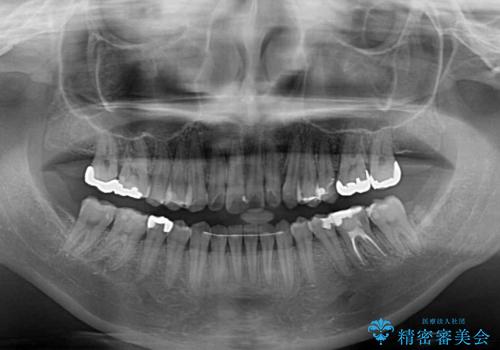

- 前歯の捻れを気にして来院された患者様です。

上顎前歯が捻れて前方に飛び出しており、下顎前歯もそれに沿うようにデコボコとなっていました。

IPR(歯と歯の間を削る処置)によりスペースを獲得して上下前歯のデコボコを改善し、インビザラインにて矯正治療を行うこととしました。

捻れていた前歯の形態が、先端が欠けていたり、一部むし歯処置により左右非対称の形態となっていたため、なかなかゴールが定まらず、治療期間がかかってしまいました。